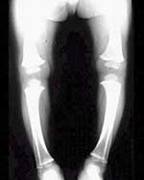

那么罗圈腿又是怎样引起的呢?医学上称罗圈腿为"O"型腿,是小儿常见的维生素D缺乏性佝偻病的一种表现。该病主要致儿童骨钙化障碍,以及钙不能沉着引起骨样组织堆积,使儿童生长期骨骼改变、肌肉松驰。6~12个月小儿发病最多,2岁以后渐少,"O"型腿发生在站立以后的佝偻病患儿,由于腿长骨钙化不良,站立、行走时身体重量压于腿骨使之弯曲,双膝关节向外移不能并拢而形成"O"型腿。